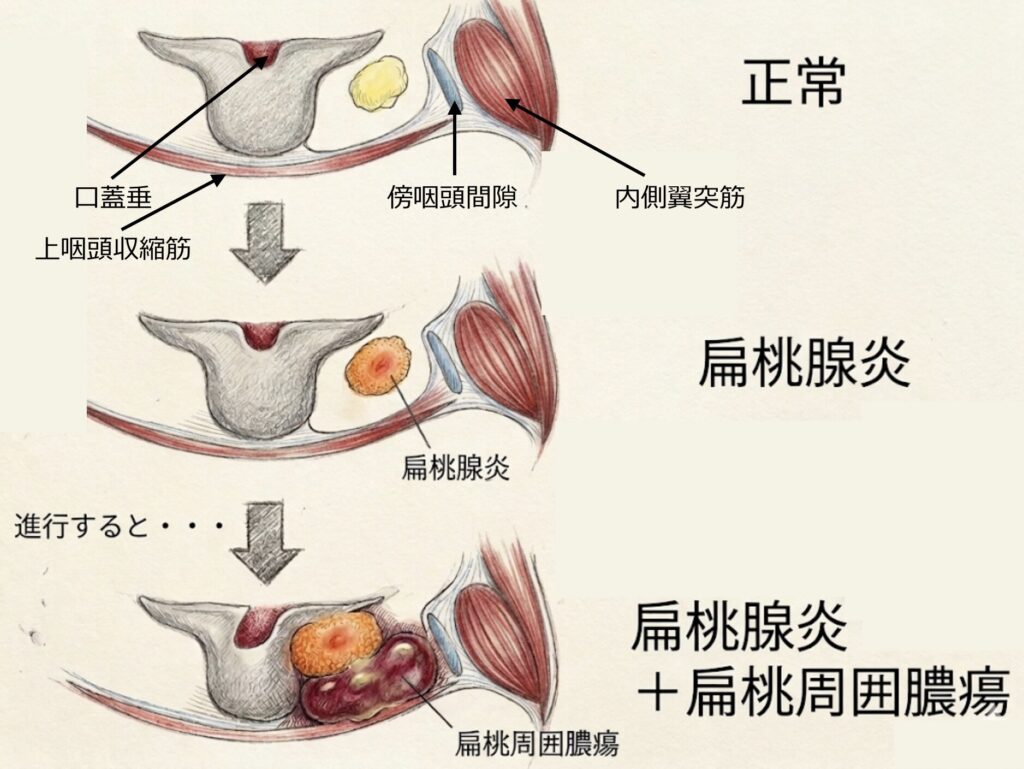

扁桃周囲膿瘍(Peritonsillar Abscess)

扁桃周囲膿瘍は、口蓋扁桃の細菌感染が扁桃被膜を越えて周囲へ波及し、被膜と咽頭収縮筋との間に生じた蜂巣炎(扁桃周囲炎)が進行して、同部位に膿瘍を形成した病態です。

臨床症状・身体所見

- 通常は一側性に発症し、先行する急性扁桃炎からさらに増悪した著明な咽頭痛および嚥下痛を呈し、患側の耳や頸部への放散痛を伴います 。

- 全身倦怠感や食欲不振のほか、音声は含み声となります 。

- 炎症が翼突筋などの咀嚼筋に及ぶと、開口障害をきたします。